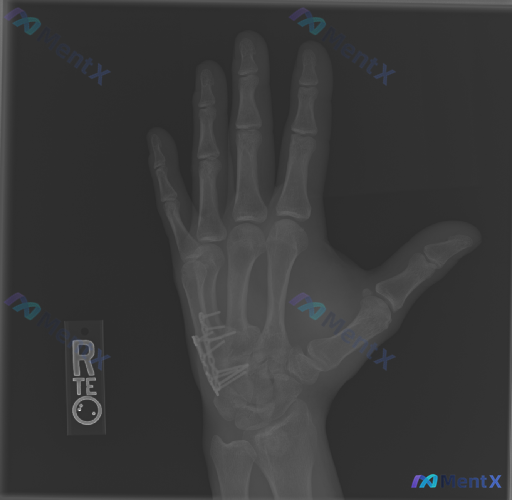

整理到一份右手正位X光的影像资料,情况如下: - 背景:第5掌骨基底部骨折,行切开复位内固定术后 - 影像所见: - 第5掌骨基底部可见金属钢板及多枚螺钉,位置良好,未见明显松动或断裂 - 该部位骨折线模糊,提示已进入骨愈合期 - 其余掌骨、指骨及腕骨骨皮质连续,未见明显新鲜骨折或骨质破坏 - 关节...